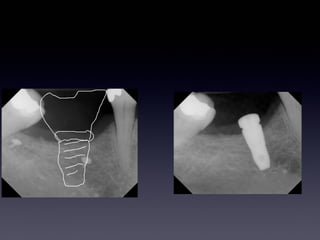

> Case 2

SMARTbuilder

POD 24 weeks 2nd Stage surgery